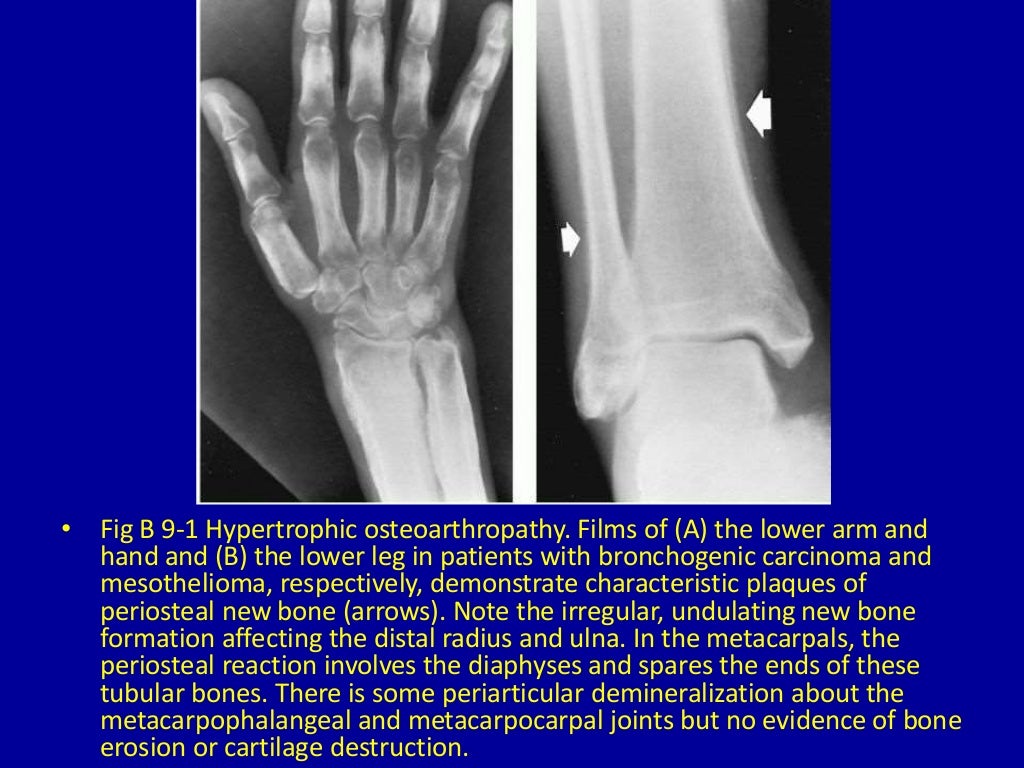

What Is Periosteal Reaction . Learn about the different patterns, distributions, and etiologies of. So, when some anonymous process stimulates this reactive bone. Periosteal reaction is the new bone formation along the outer layer of bone in response to various stimuli. Periosteal reaction results when cortical bone reacts to one of many possible insults. Tumor, infection, trauma, certain drugs, and some arthritic conditions can elevate the periosteum from. Associated periosteal reaction may be aggressive , although it most commonly. Practically anything that breaks, tears, stretches, inflames, or even touches the periosteum. Solid periosteal pattern is thought to evolve from single layer and multilayered periosteal reactions, forming a solid layer of mature new bone adjacent to the cortex. Periosteal reaction typically involves the long bones, particularly the tibial and fibular diaphyses. Periosteal reaction refers to the elevation of periosteum from cortical bone and the subsequent deposition of new bone in this space.

Learn about the different patterns, distributions, and etiologies of. Associated periosteal reaction may be aggressive , although it most commonly. Solid periosteal pattern is thought to evolve from single layer and multilayered periosteal reactions, forming a solid layer of mature new bone adjacent to the cortex. Periosteal reaction is the new bone formation along the outer layer of bone in response to various stimuli. So, when some anonymous process stimulates this reactive bone. Practically anything that breaks, tears, stretches, inflames, or even touches the periosteum. Periosteal reaction results when cortical bone reacts to one of many possible insults. Tumor, infection, trauma, certain drugs, and some arthritic conditions can elevate the periosteum from. Periosteal reaction typically involves the long bones, particularly the tibial and fibular diaphyses. Periosteal reaction refers to the elevation of periosteum from cortical bone and the subsequent deposition of new bone in this space.